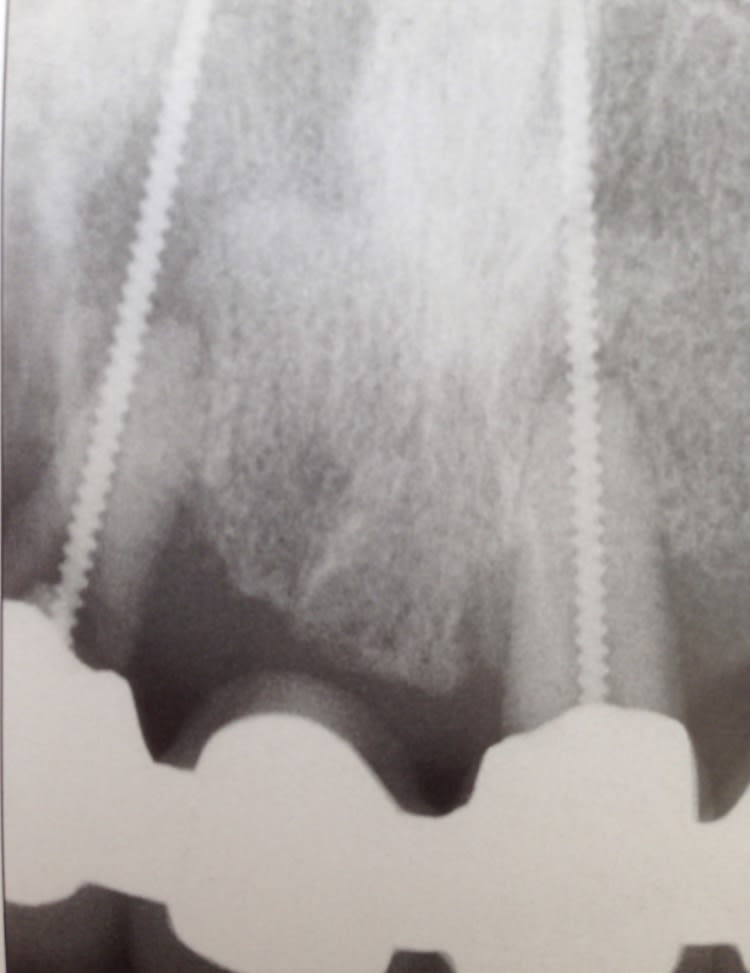

un protapergold bleu cassé par votre serviteur sur une incisive latérale impossible a sortir (infra osseux de 3mm) avec les masseran

voili voila

j'ai un microscope

j'ai bousillé mes masseran

aucune chance de sortir ca en retrograde

suis un peu desarme

La c 'est sûr t'emmerde pas à acheter le frag remover tu n'y arriveras pas avec

Ton protaper a transfixé l'apex donc il est bien fixé dedans. tu peux envoyer à un endo exclusif. Instrument difficile à sortir selon moi mais faisable avec de la patience et des ultrasons adaptés

Ho ho.... Pas facile... Sur une racine gracile en plus...